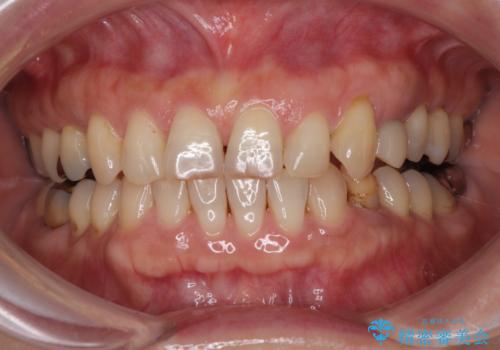

- 「最近、左下の歯がぐらぐらしてきて不安…」

そんなお悩みをきっかけにご来院された50代女性の患者様の症例です。

診査の結果、左下に残存していた乳犬歯が水平的に破折しており、残念ながら保存は困難な状態でした。

また、右下にはスペースがあり、左上にも乳犬歯が残存しているという状態で、治療方法としては矯正治療を含めた複数の選択肢が考えられました。